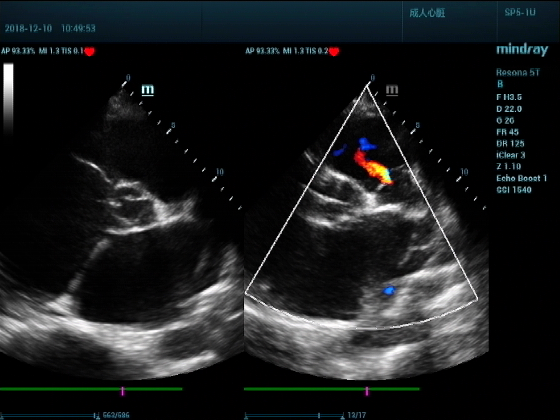

病例二:

男,81岁,全身浮肿来住院

超声可见:左房,右房,右室明显增大,主肺动脉及右肺动脉增宽,二尖瓣中度反流,三尖瓣重度反流,肺动脉轻度高压,心律不齐

心包积液盆腔积液。淤血性肝增大,肝静脉增宽。(右心衰声像改变)